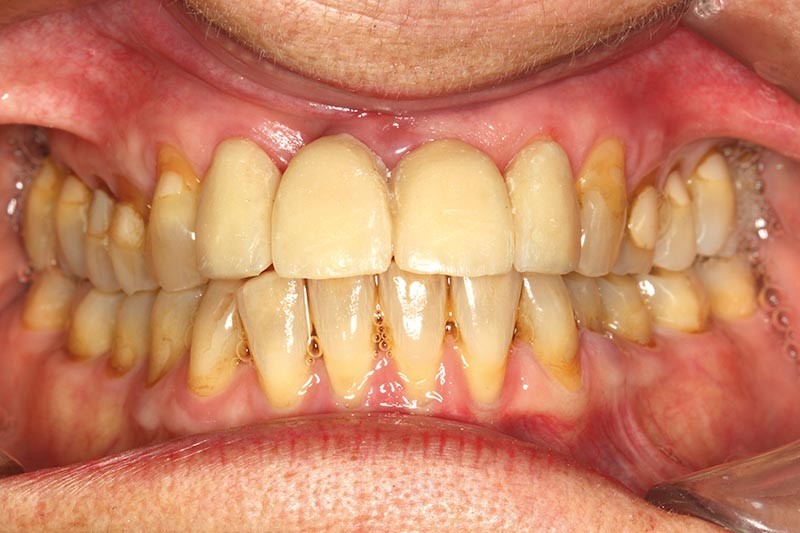

Une patiente présente un proglissement mandibulaire aboutissant à une inversion d’occlusion au niveau des incisives (fig. 2).

Au-delà du préjudice esthétique, il induit des forces importantes en direction vestibulaire sur les incisives mandibulaires. Ces incisives présentent une légère mobilité. La radio rétro-alvéolaire montre un élargissement desmodontal et une perte osseuse verticale sans cratérisation ni inflammation (fig. 3).

Un montage en articulateur des moulages permet d’observer en relation centrée (RC) de meilleures conditions d’affrontement des dents antérieures. La proposition thérapeutique est la réfection du bridge existant, une équilibration occlusale par coronoplastie des secteurs postérieurs pour stabiliser les appuis occlusaux en RC et la mise en place d’une contention dans le secteur antérieur mandibulaire. Une maquette prothétique permet la réalisation d’un bridge provisoire dans une position corrigée (fig. 4).